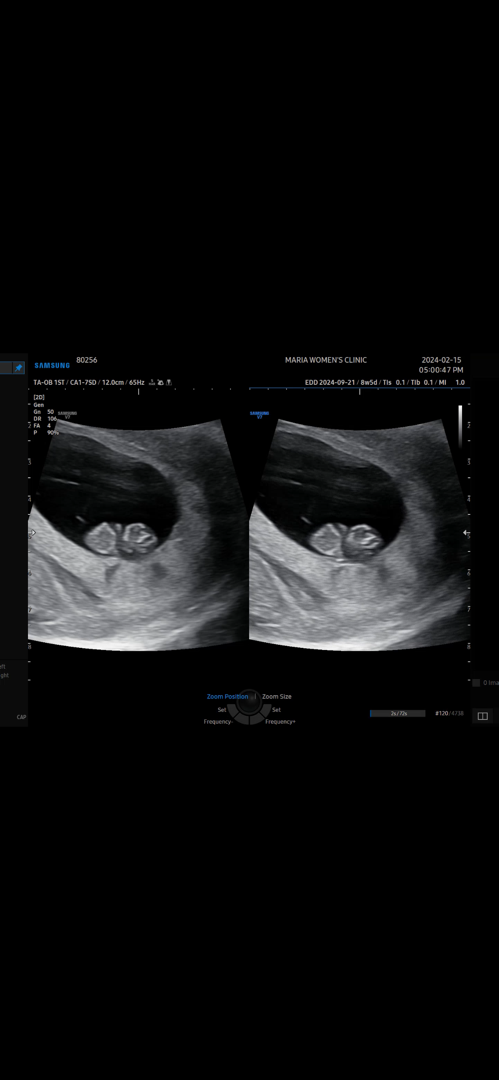

우래기 8주5일차 젤리곰🐻💕

2주만에 갔는데 몸통이랑 머리 분리되고 손,발이 보이더라구요ㅠㅠㅠㅠ감격,, 친정엄마랑 같이 갔는데 아는건지 손을 막 휘젓더라구요🤣 다음은 3주 뒤에 오라는데 얼마나 커있을지 기대되요!!!